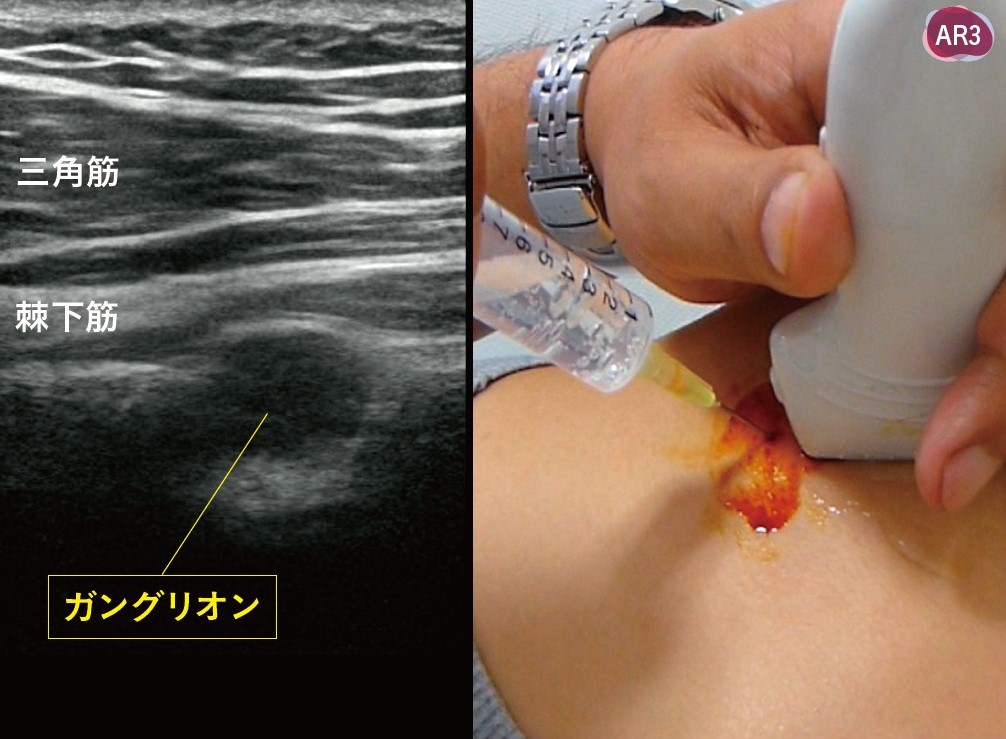

ガングリオン

超音波ガイド下に正確にガングリオンを同定し針を刺入してゼリーを吸引します(右図は希な肩甲切痕部ガングリオン)